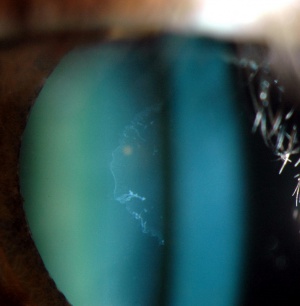

The classic sign of PXF is the visualization of white pseudoexfoliative material on the pupil margin and on the anterior lens surface (with a clear intermediate zone due to rubbing off by the iris). This is most easily seen after dilatation, and is therefore sometimes overlooked (Figures 1-6). Approximately 20% of the cases can be missed in undilated eyes. The material may be seen on the conjunctiva, corneal endothelium, lens zonules, ciliary processes, and trabecular meshwork. In pseudophakic and aphakic eyes, it may be deposited on intraocular lens and the vitreous face, respectively.

Figure 1: Left eye of a patient with PXF glaucoma. Note the the white pseudoexfoliative material on the central anterior lens capsule, surrounded by a clear zone (caused by iris rubbing)

Figure 2: Left eye of a patient with PXF glaucoma. Note the white pseudoexfoliative material on the periphery of the lens capsule and the inner clear zone caused by iris rubbing. This would not be visualized through an undilated pupil.